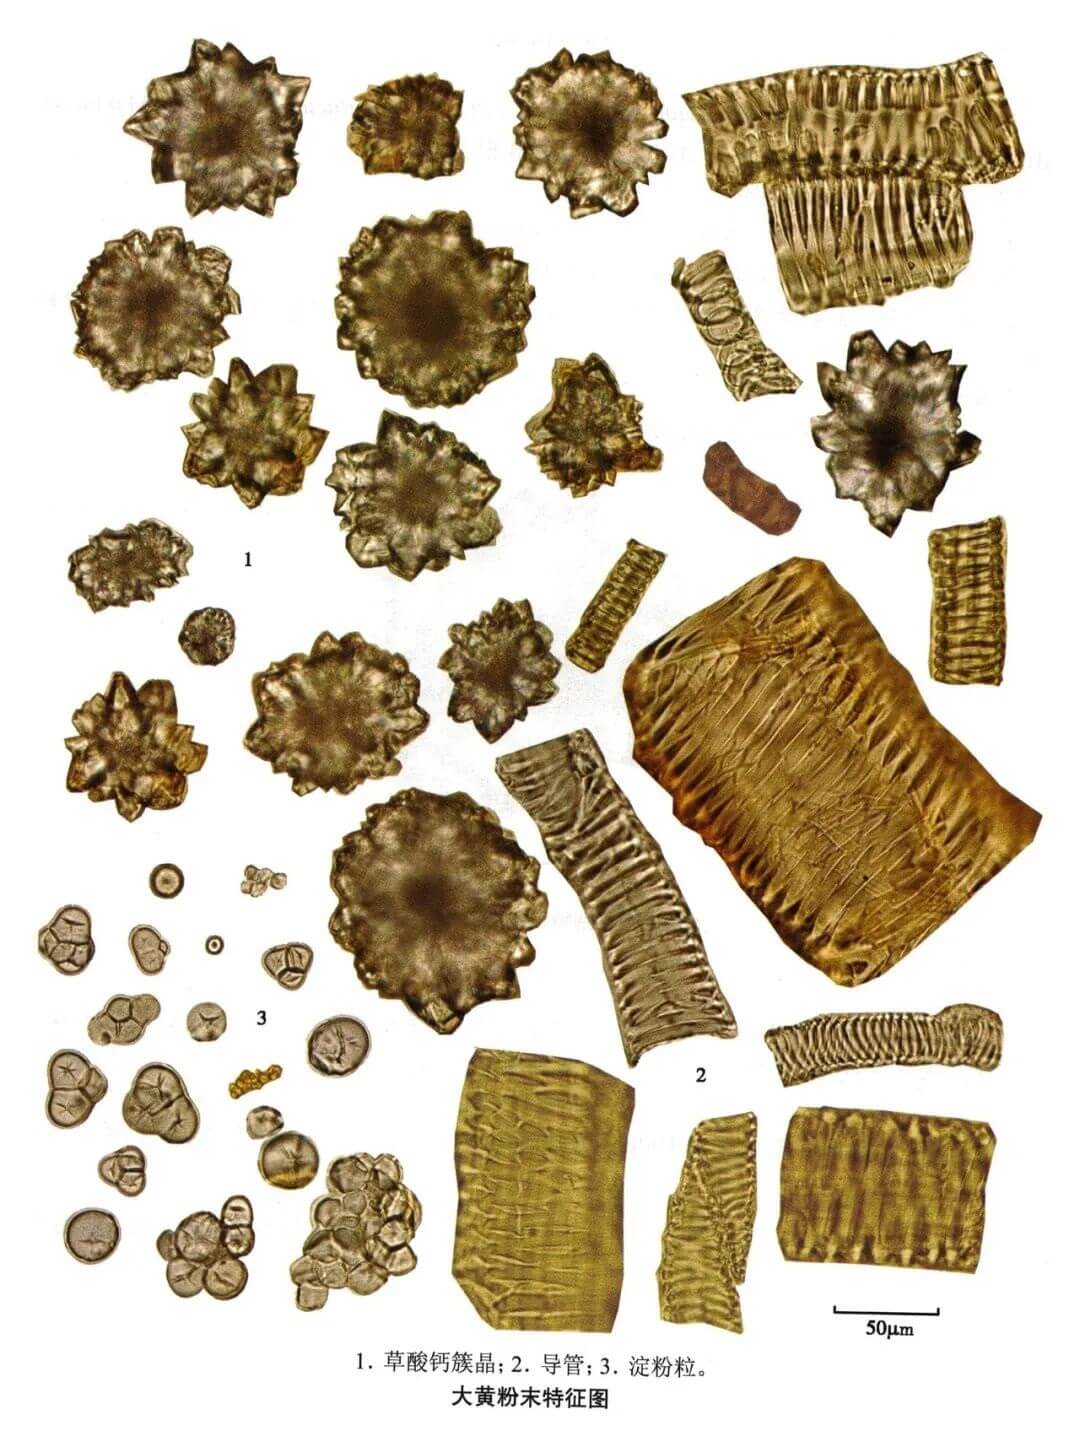

大黄

| 大黄 |

|---|

| 【参考标准】《中国药典》2020年版一部 |

| 【显微鉴别】 粉末黄棕色。草酸钙簇晶直径20~160μm,有的至 190μm。具缘纹孔导管、网纹导管、螺纹导管及环纹导管非木化。淀粉粒甚多,单粒类球形或多角形,直径3~45μm,脐点星状;复粒由2~8分粒组成。 |

| 【显微重点】 草酸钙簇晶甚大,且数量较多。 |

| 【图谱来源】 《中药成方制剂显微图典》 |